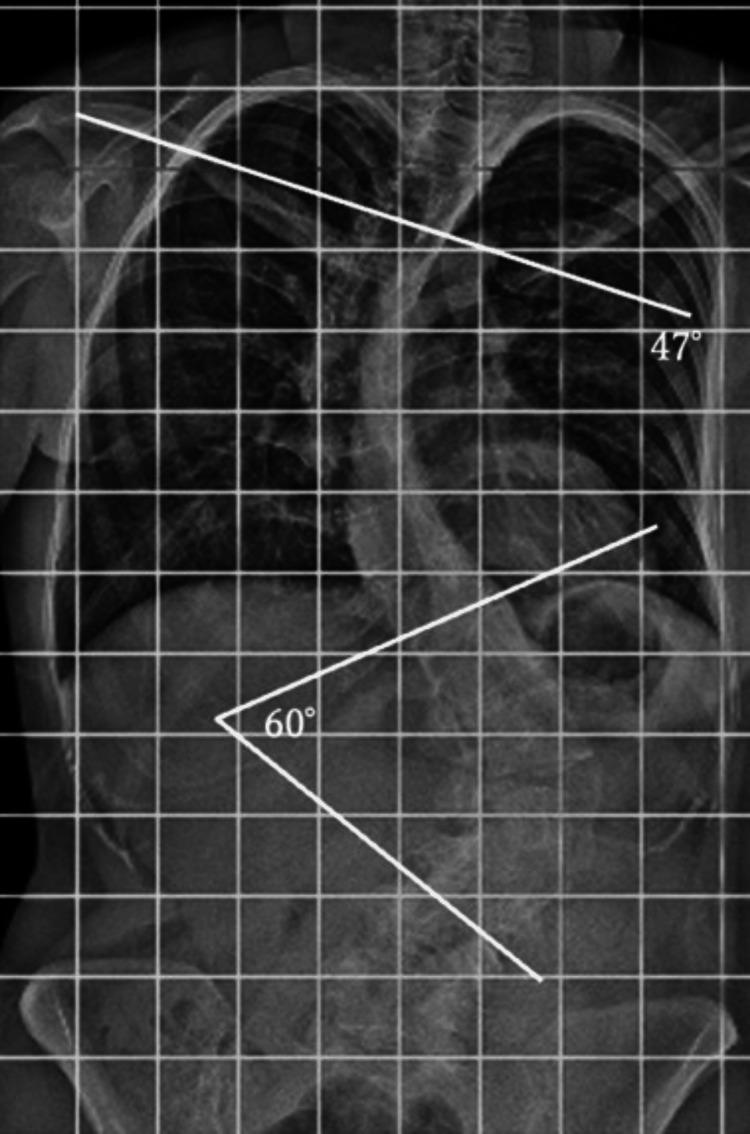

Lumbar spine instability fractures in patients with residual adolescent idiopathic scoliosis (AIS) are rare, and optimal treatment strategies remain unclear. Surgical management must consider both immediate fracture stabilization and the potential need for future scoliosis correction. A 24-year-old woman with residual AIS (Cobb angles: 47° thoracic, 60° lumbar) sustained an AO Spine Classification Type B2 lumbar fracture (L2) after falling from the second floor. She presented with severe back pain but no neurological deficits. Radiographic evaluation confirmed vertebral body collapse and posterior ligamentous injury. Posterior fixation alone was chosen over combined anterior-posterior fixation to maintain future options for scoliosis correction. The patient recovered uneventfully, achieving solid bone fusion by seven months postoperatively, at which time the implants were also removed. At the two-year follow-up, she remained asymptomatic with no progression of scoliosis or instability. For lumbar fractures in patients with residual AIS, surgical decision-making should consider future scoliosis management. Posterior fixation alone may be a viable strategy to ensure both stability and surgical flexibility.

残留青少年特发性脊柱侧凸(AIS)患者的腰椎不稳定骨折较为罕见,最佳治疗策略仍不明确。手术治疗必须兼顾即刻的骨折稳定以及未来脊柱侧凸矫正的潜在需求。一名24岁残留AIS(Cobb角:胸椎47°,腰椎60°)的女性从二楼坠落,发生AO脊柱分类B2型腰椎骨折(L2)。她表现为严重背痛,但无神经功能缺损。影像学评估证实椎体塌陷和后韧带损伤。选择单纯后路固定而非前后联合固定,以保留未来脊柱侧凸矫正的选择。患者恢复顺利,术后7个月实现了牢固的骨融合,此时植入物也被取出。在两年随访时,她无症状,脊柱侧凸或不稳定均无进展。对于残留AIS患者的腰椎骨折,手术决策应考虑未来的脊柱侧凸治疗。单纯后路固定可能是确保稳定性和手术灵活性的可行策略。